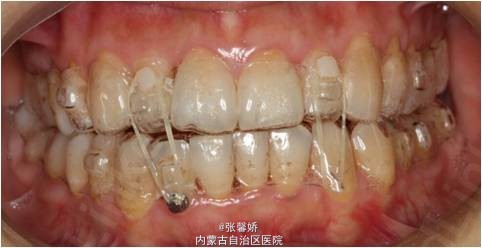

上中线右偏1mm,A2、D4反合,A2、B2畸形牙偏小,拥挤度上颌4mm、下颌6mm。Spee曲线:左侧3mm,右侧2.5mm

牙列中度拥挤;A2、D4反合 处理:时代天使隐形矫治器矫治 拔除C8、D8 适当下前牙邻面去釉 排齐整平上下牙列,改正A2、D4反合 治疗时间2年左右,矫治后牙齿排列整齐,咬合关系良好,患者满意。